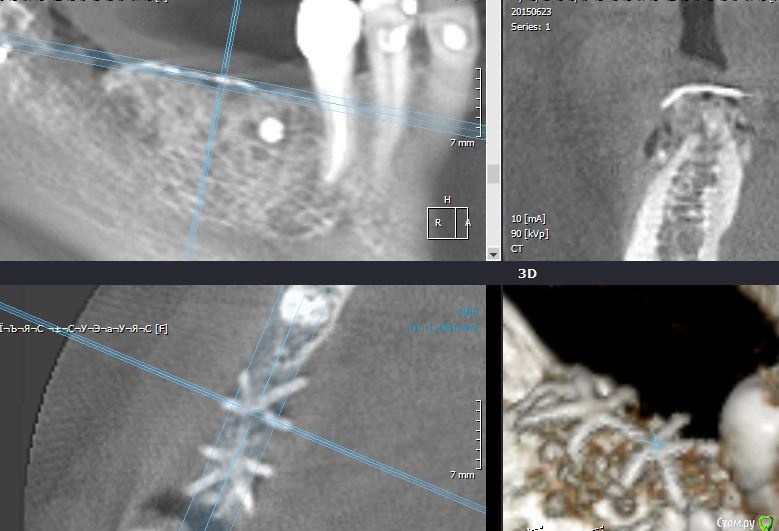

Endorphin Опубликовано 21 декабря, 2015 Автор Поделиться Опубликовано 21 декабря, 2015 Пора КТ показать. Изначально рассчитывал на большее, но на фоне осложнений, думаю, и это хороший результат. Имплантата в позиции 46 так дистально расположен именно из-за недостатка кости. В январе-феврале установка. Ссылка на комментарий

Endorphin Опубликовано 30 января, 2016 Автор Поделиться Опубликовано 30 января, 2016 Сделайте фото когда ставить будете, очень интересноСделал.Результат превзошел ожидания. Из-за изначально неправильного расположения мембраны и графта, "ширина" начинается лишь отступя 6.5 мм от шейки 45, так что центр платформы дистализирован для моляра (8.5мм когда хочется 6мм). Качество фото так себе, но суть, думаю, ясна - кость наросла в достаточном объеме и качестве, торк > 45. Обязательно ССТ под швы. Еще раз всем спасибо! 1 Ссылка на комментарий